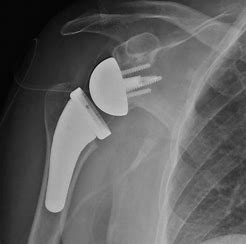

The final surgery of the day was a total reverse shoulder. By this time the surgeon and PA were used to having me around. They asked a nurse to get me a stool and let me stand REALLY close. I could see right into the glenoid fossa and could see everything. I even got splashed with a little blood. The patient's femoral head was very large and mis-shapen but it wasn't an issue when they hollowed out the end for the ball to fit into. It was a very interesting surgery and was done in 40 minutes!